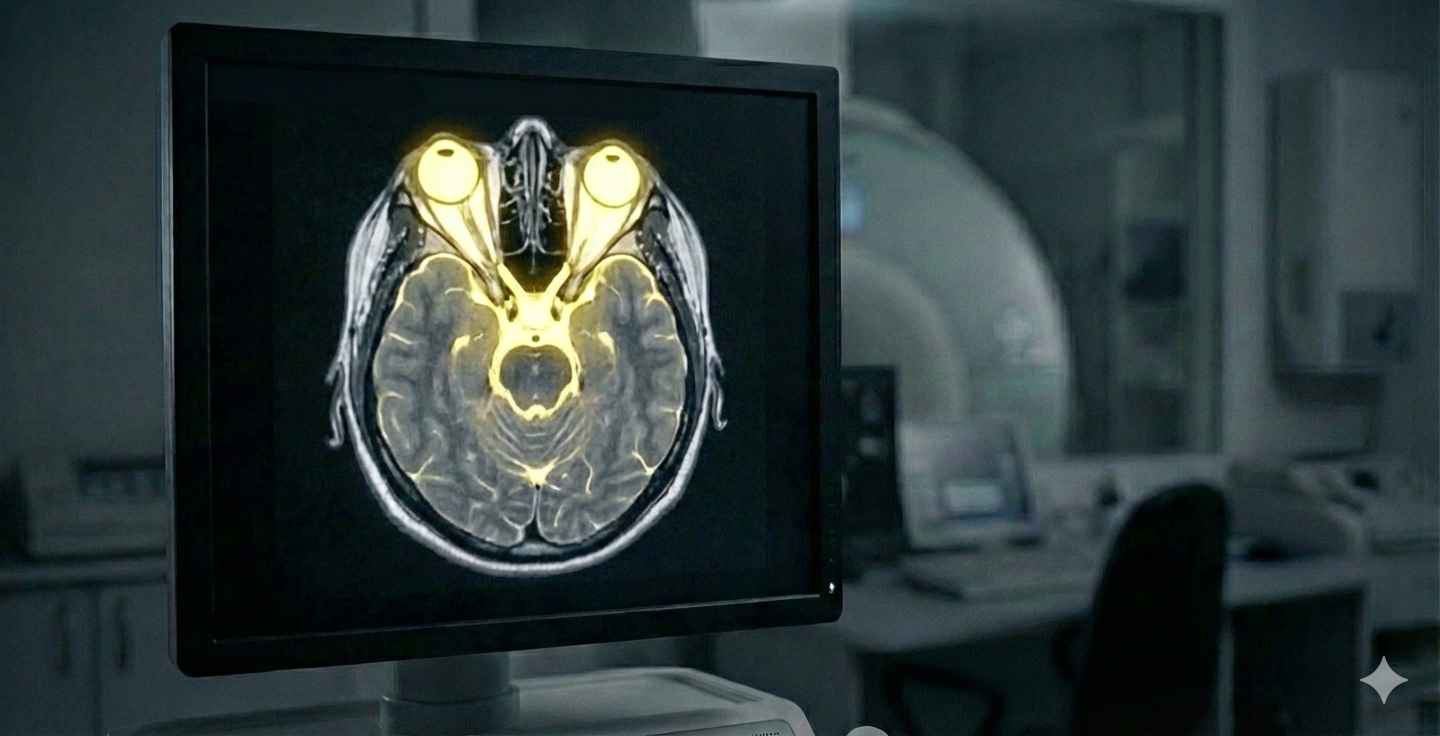

Це найбільш інформативний метод дослідження шиї, який створює детальні 3D-зрізи хребців, міжхребцевих дисків та спинного мозку. На відміну від рентгену, МРТ «бачить» не лише кістки, а й м’які тканини. Це дозволяє нам точно діагностувати:

Чому важливо робити МРТ шиї з контрастом? Контрастна речовина «підсвічує» активні вогнища хвороби. Це дозволяє лікарю зрозуміти: хвороба зараз у стані загострення чи в ремісії. Потужність нашого апарату 1.5 Тесла критично важлива для пошуку найдрібніших осередків, які можуть «пропустити» слабші сканери. МРТ-апарат Philips Achieva створює надчіткі 3D-зображення внутрішніх органів та систем у рекордно короткі терміни. Це означає, що ви проводите в апараті менше часу, отримуючи при цьому максимально деталізований результат.